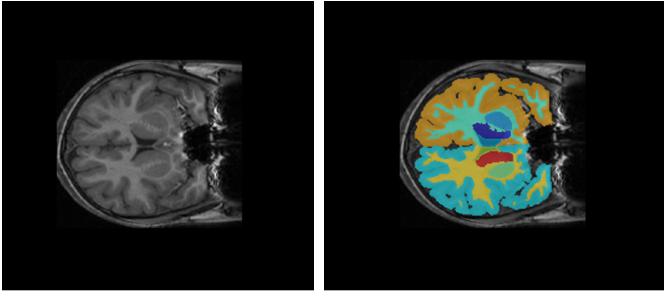

Child and Adolescent NeuroDevelopment Initiative (CANDI) neuroimaging data set

| The CANDI data set (subset HC_001) contains one brain MRI image volume and its corresponding segmentation label image [27]. The total size of the data set is approximately 2.5 MB. Download the CANDI data set from the MathWorks website. zipFile = matlab.internal.examples.downloadSupportFile("image","data/brainSegData.zip"); filepath = fileparts(zipFile); unzip(zipFile,filepath) dataDir = fullfile(filepath,"brainSegData"); For an example showing how to load and process this data for deep learning, see Brain MRI Segmentation Using Pretrained 3-D U-Net Network | Semantic segmentation |